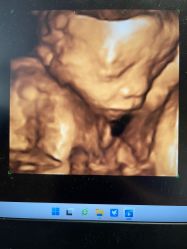

• -北京俪婴妇产医院(朝阳大悦城店)

相册

T9 上传于 22-07-02 | 报错